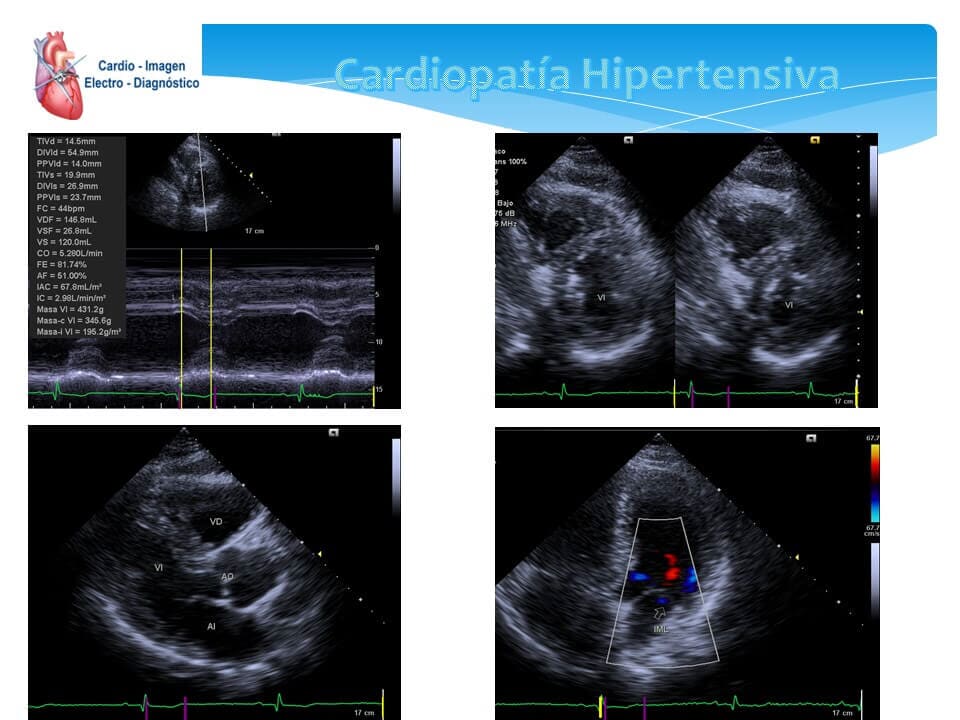

- Ecocardiograma transtorácico

- Ecocardiograma Doppler

- Ecocardiograma bidimensional

- Ecocardiografía